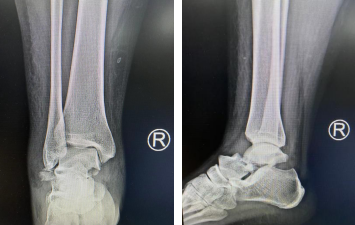

术前X线片,距骨骨折伴脱位